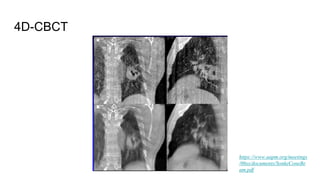

4D-CBCT

https://www.aapm.org/meetings

/06ss/documents/SonkeConeBe

am.pdf